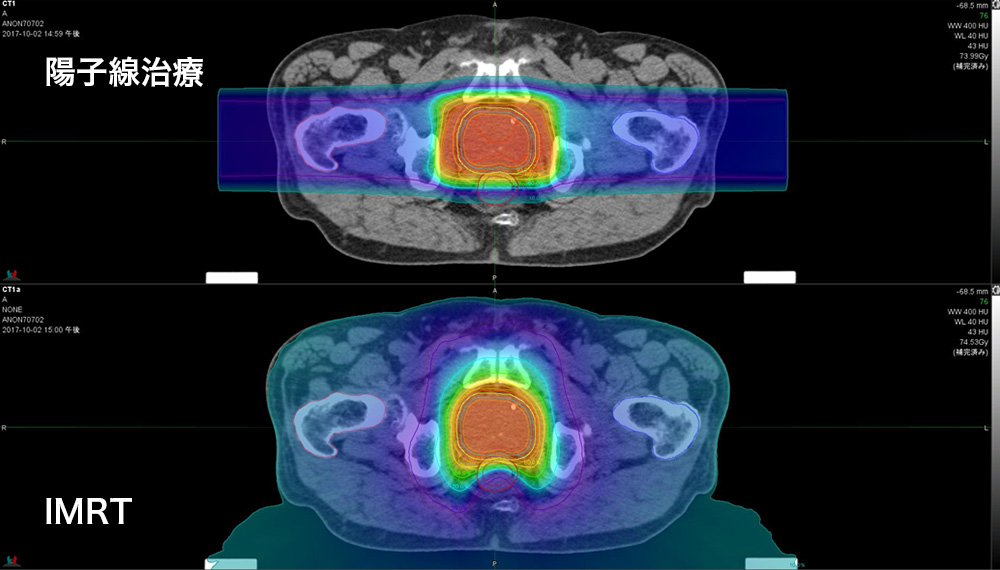

陽子線治療では、放射線は陽子線で照射されます。 X 線との主な違いは、陽子線はエネルギーをターゲットに届けると停止することです。

陽子線治療を使用することで、医師は周囲の組織に損傷を与えるリスクを減らしながら、より正確かつ強力に前立腺がんを標的にすることができます。

ペンシルビームスキャニング陽子線治療を使用すると、医療専門家は陽子線をより広範囲に操作し、集束させることができます。これにより、二重散乱療法よりも正確な線量が得られ、周囲の組織をさらに節約します。

陽子線治療では放射線が集中しているため、通常は従来の放射線治療よりも副作用が少なくなります。それは、腫瘍周囲の健康な組織への損傷が少ないためです。